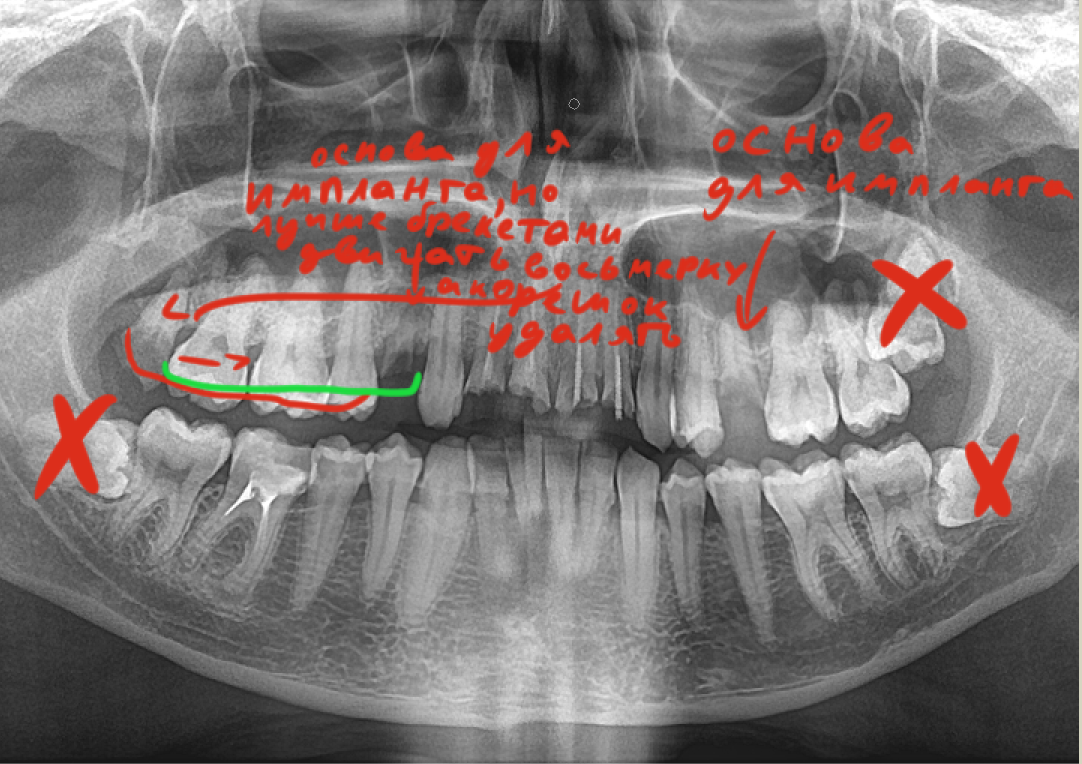

Screenshot20250[...].jpg 244Кб, 720x1600

720x1600

175879209708150[...].jpg 1246Кб, 2640x1980

2640x1980

Двач скажи, мне гг или ещё можно что-то спасти?

Зубы вроде не болят, но в стоматологии сказали везде кариес, половину зубов пломбировать...

Ещё и чистку сказали сделать, за 8к...

Крч посоветуйте что-то, не сделают ли хуже в гос.стоматологии...

Аноним 25/09/25 Чтв 13:25:03 1641753 170

>>1641746

хуже чем ты сделал наверно уже не будет, хз в каком там состоянии зубы, но на вскидку тебе надо удалять 2 нижних восьмерки(при том тебе скорее всего будут долбить десну чтоб горизонтальные удалить) и одну верхнюю, оставшуюся брекетами двигать если удалить огрызок, но если не готов прям щас в брекеты идти огрызки не удаляй т.к. они могут послужить основной для импланта, кроме восьмерок просто так ничего удалять не надо, очевидно это огромные бабки по нынешним временам и много усилий, если хочешь прям восстановить рот это надолго и надорого и я сомневаюсь что ты что то из этого потянешь, для человека который себя так запустил я вобще удивлен что тебя такое волнует или тебя сбил камаз и ты очнулся в теле этого бича маргинального? там наверно еще и десны воспалены(так что после чистки и заделывания кариеса к парадантологу пиздуй), действительно сперва чистка(8к это в каком городе? в нск 3,5 в гос стоматологии) и лечение кариеса, а потом..ну я бы задумался в сторону путешествия в другую страну для лечения типо дешевле, слышал краем уха про такое но подробностей не знаю, ну а так скорее всего это протезирование и видимо оно будет упираться в твои бюджеты чем дороже тем больше своих зубов или то что от них осталось сохранишь, ну а так это риально пиздец, даже у бамжей с зубами лучше